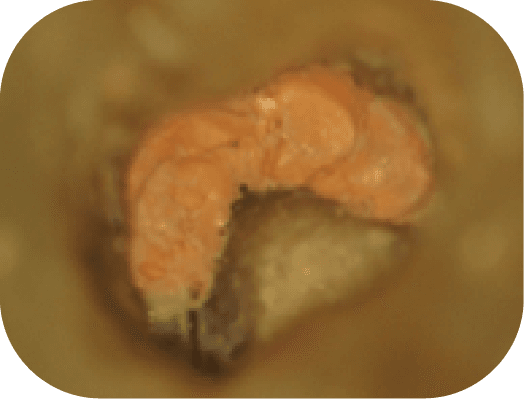

病人因其他院所醫師無法定位根管位置被轉診,在顯微鏡底下可以發現短短不到兩毫米的距離藏有兩根根管(圖中紅線標示處),這是傳統根管治療很難發現的。

一般來說我都會建議只要是後牙都可以使用顯微鏡去處理,每顆牙齒都是獨一無二的,用顯微鏡的好處是讓醫師不用去猜有幾根根管或是根管在哪,而是更有底氣的去做好治療。